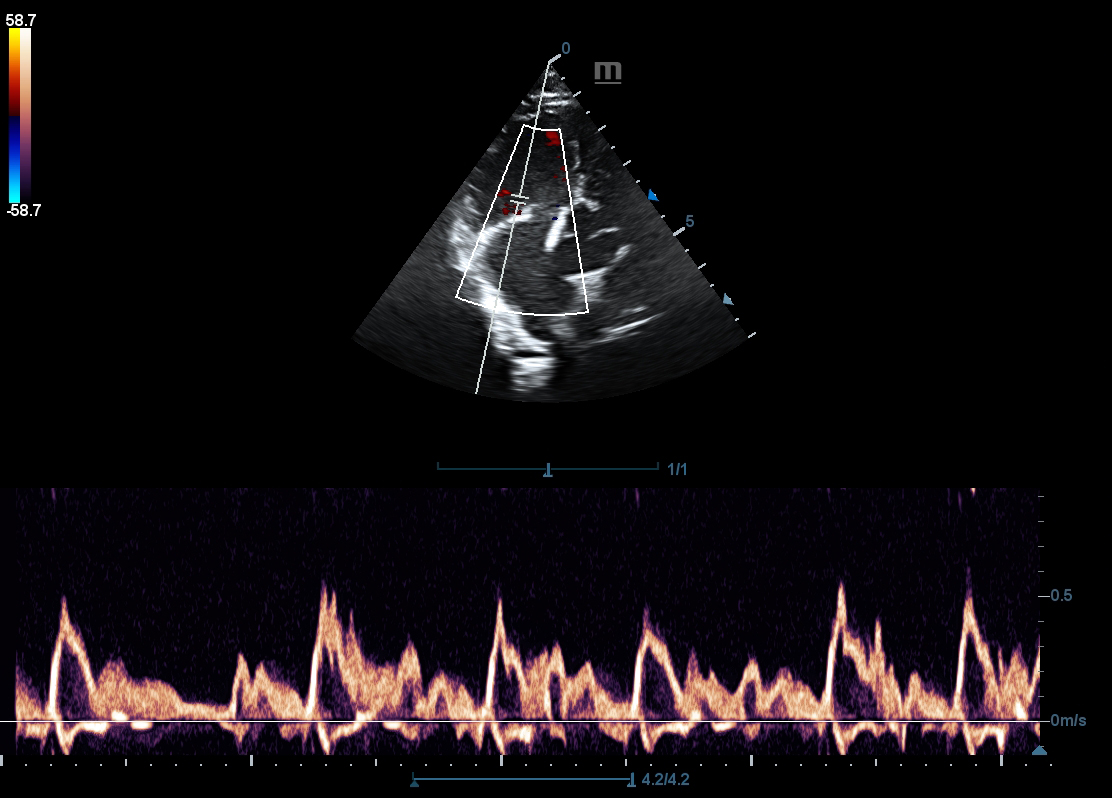

PW

PW Doppler and Auto Trace reveal details of blood flow for more comprehensive diagnosis.